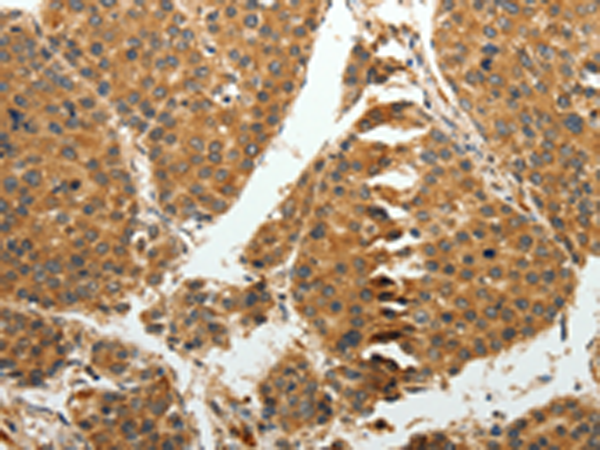

IHC positive control:

Human liver cancer and human tonsil

IHC Recommend dilution:

25-100